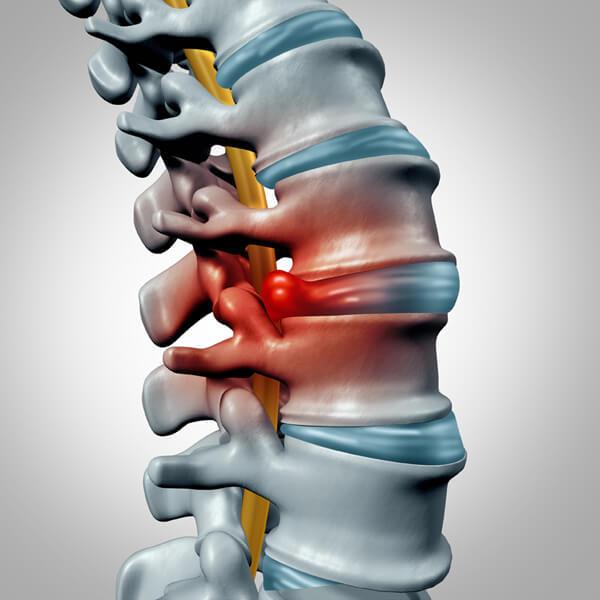

추간판탈출증

추간판탈출증은 추간판이 돌출되어 요통 및 신경 증상을 유발하는 질환이다. 즉, 추간판 내부의 젤리 같은 수핵이 탈출하여 주변을 지나는 척추신경을 압박함으로써 다양한 신경학적 이상 증상을 유발한다. 우리에게 "디스크"라고 잘 알려진 질환이 바로 추간판탈출증이며, 주로 점진적 퇴행과 관련이 있어 정상적인 노화 과정이나 외상에 의해 발생한다.